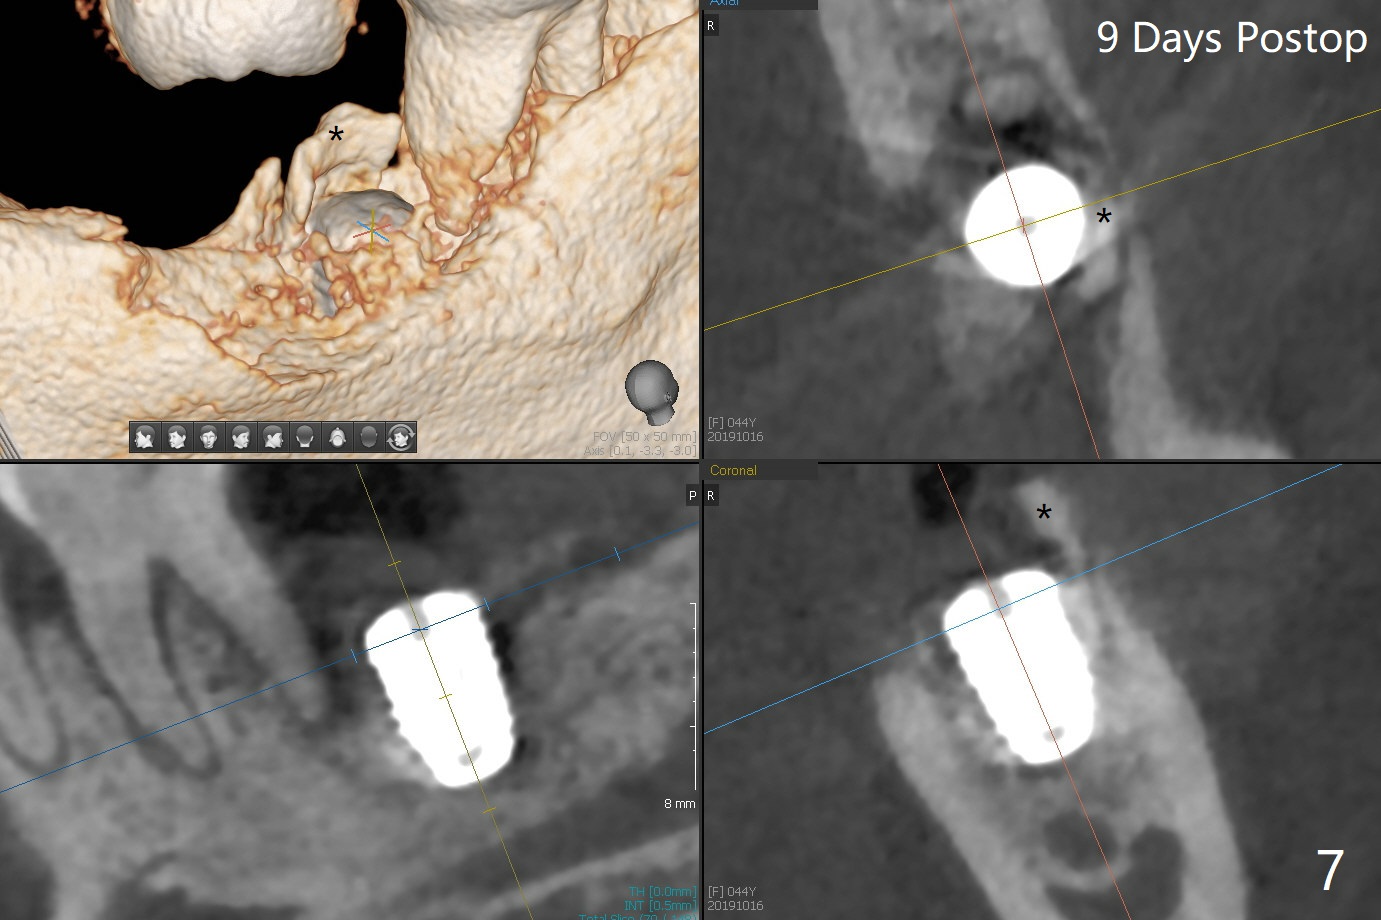

Socket shield (partial extraction therapies) is going to be conducted in this case to form a substitute buccal plate of the 2nd molar (Fig.1 *). The apex of the shield that contacts the 4.5x10 mm dummy implant cannot be removed because of poor access (Fig.2 * (12 mm offset)). Due to high bone density, a 4.5 mm drill has to be used in order to place a 5x7.3 mm definitive implant (Fig.3). In spite of the fact that the implant seems to be completely seated, the implant is ~ 1 mm supracrestal lingually. After implant removal, a 4.5x11.5 mm drill cannot reach the depth due to high bone density. 800 RPM instead of 50 RPM may help. When the implant is reseated, it appears to be .5 mm deeper than before clinically, although it looks incompletely seated in X-ray (Fig.4 <). The insertion torque is 60 Ncm. Allograft mixed with PRF is placed around the implant with cover screw, particularly mesiolinguodistal (Fig.4 *). The sockets of #17 and 18 are approximated with the help of 2 piece of PRF and collagen plug. The wound dehisces 9 days postop (Fig.5,6), although asymptomatic. Forced closure of the sockets with suture seems unnatural. An immediate provisional should have been fabricated. CT shows possible loss of part of bone graft (Fig.7). Regraft seems necessary in the appointment of uncover. Antibiotic is prescribed for another week. The gingiva seems healthy around the exposed healing screw 16 days postop (Fig.8). After debridement, the healing screw is then changed to a 4.5x5 mm healing abutment. The majority of the bone graft is lost without immediate provisional in 4 months (Fig.9 * (<: socket shield)). Then a 5.5x5 mm healing abutment is inserted for impression next appointment. A 5.2x4.5(4) mm cemented abutment is placed before impression (Fig.10). With socket shield (Fig.11 ^), the buccal gingiva looks more keratinized than the lingual one (Fig.12 *). Photos are taken immediately pre-cementation. Socket shield (*) covers the implant and abutment buccally (Fig.13 CT taken immediately pre-cementation).